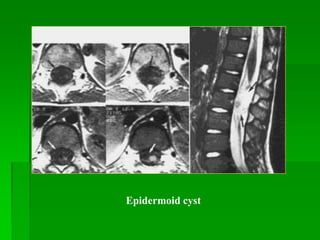

EPIDERMOID

CYST (nang

thƣợng bì)

- Bẩm sinh hay mắc phải sau chọc dò tủy sống (nang bẩm sinh hay gặp ở

chóp tủy hay chùm đuôi ngựa, nang mắc phải hay gặp ở vùng thắt lưng

thấp).

- MRI: điển hình nang đồng tín hiệu hay tăng nhẹ tín hiệu so với dịch

não tủy trên tất cả các xung.

Epidermoid cyst